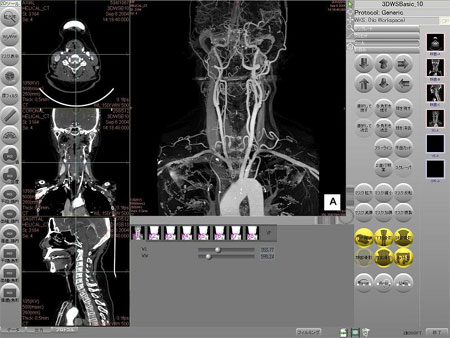

アミン・ザイオブースでは独立型ワークステーション『ZIOSTATION』、ネットワーク型ワークステーション『ZIOSTATION System1000』を展示いたします。

ネットワーク型ワークステーションSystem1000は『どこでも自由に画像処理!』をテーマに開発を進めてまいりました。ブースでは画像処理サーバーに接続された複数台のPCでボリュームレンダリング処理をはじめ各種解析を体験していただけます。

30分に1回、ネットワーク型ワークステーションSystem1000の実演デモを行います。自由に参加できますのでPCからの同時アクセスを試す絶好の機会です。是非、皆さんで参加していただき高速処理、高機能をご確認ください。

64bitCPU対応 画像処理ワークステーション『ZIOSTATION』

新たに開発したZEEK Engineにより骨の自動除去など熟練者の技術がボタンひとつで可能となりました。

豊富なアプリケーションソフトとあわせMSCTの能力を最大限に生かせる次世代ワークステーションです。